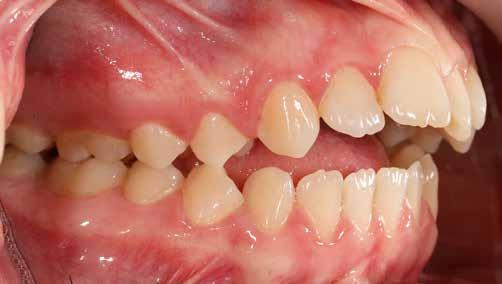

Ebben a cikkben egy 16 éves lánypáciens esetét szeretném bemutatni (1–7. képek)

A Pitts21-es fix készülékes kezelés során a harapásemelőket a felső nagyőrlő fogakra ragasztottuk, hogy a felső molárisok intrúziójával segítsék a harapás zárását (8. kép) Ún. keresztharapásos, majd később normál class 2-es gumihúzással (9–10. képek), továbbá az elülső fogakon alkalmazott ún. Rainbow harapás-záró gumihúzással (11. kép) korrigáltuk a jobb oldali teljes premolárisnyi distal-harapást, valamint az elülső nyitott harapást.